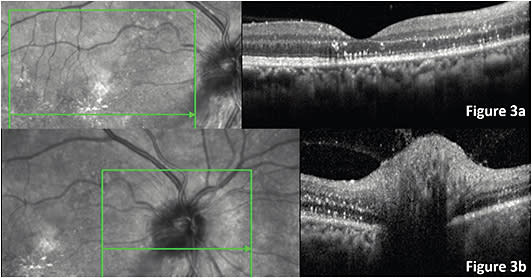

Other lab results: HIV 1 and 2 negative; Toxoplasma (IgG and IgM) non-reactive; Treponema pallidum (IgG and IgM) non-reactive; CMV (IgG and IgM) non-reactive; Bartonella henselae IgM was reactive. The patient was assessed by the neurologist and infectious disease specialist, and was admitted in the internal medicine floor. Methylprednisolone IV pulses for 3 days, and doxycycline 100 mg PO bid were started. Then prednisolone at 1 mg/kg was added for 1 week with the respective tapering indications. After 8 days of the treatment, his VA OD was 20/100, the ONH swelling was decreasing, with resolving of the subretinal fluid, but the start-shaped hard exudates persisted (Figure 3). Four weeks later, VA OD was 20/40; subretinal fluid resolved with persistence of the hyperreflective exudates.